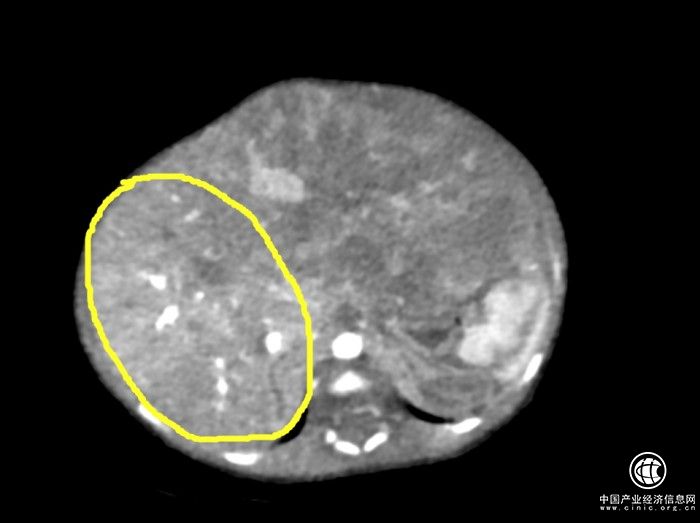

經(jīng)過多學(xué)科會診,結(jié)論是孩子的肝母細(xì)胞瘤非常大,正常肝臟被極度擠壓,隨時有破裂可能,需要盡快手術(shù)。

被腫瘤極度擠壓的肝臟